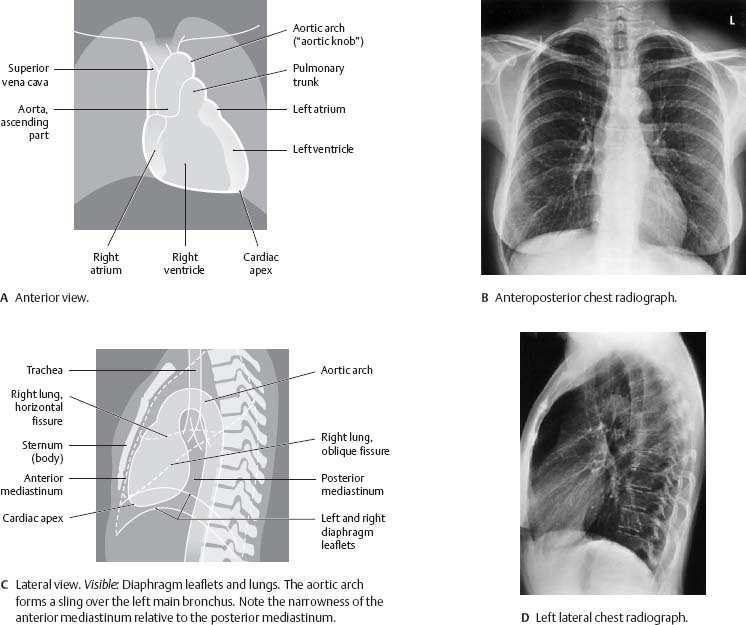

Fig. 7.21 Radiographic appearance of the heart